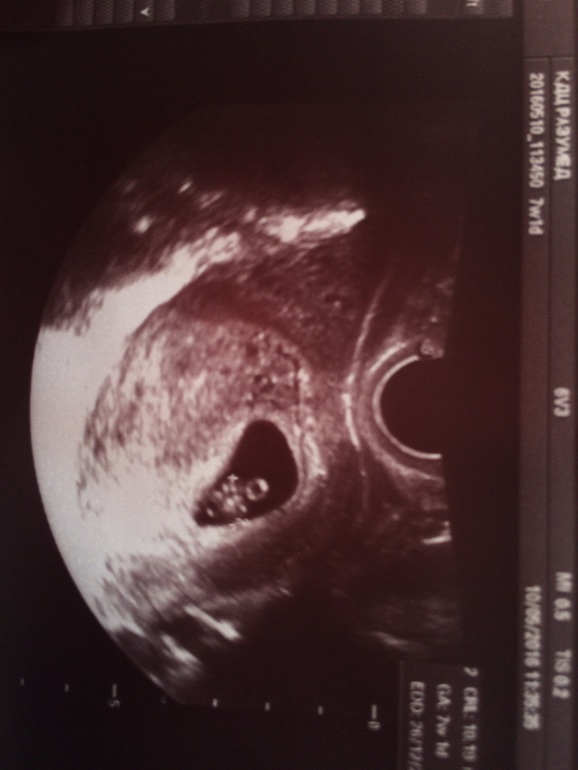

Сходила я на платное узи,дабы исключить всякие дурные мысли из моей головы!

Сходила и очень рада этому! Мало того что я увидела свою крошку,дак и ещё увидела как бьется сердечко)) очень счастлива!!!!!!😘😘😘

Вот моя бусинка!

Срок поставили 7 нед и 1 день! Соответствует акушерскому сроку!)

Мало того,что я увидела на телевизоре свою кроху,дак ещё и первое фото дали!!! Я довольна как слон!!!!🐘